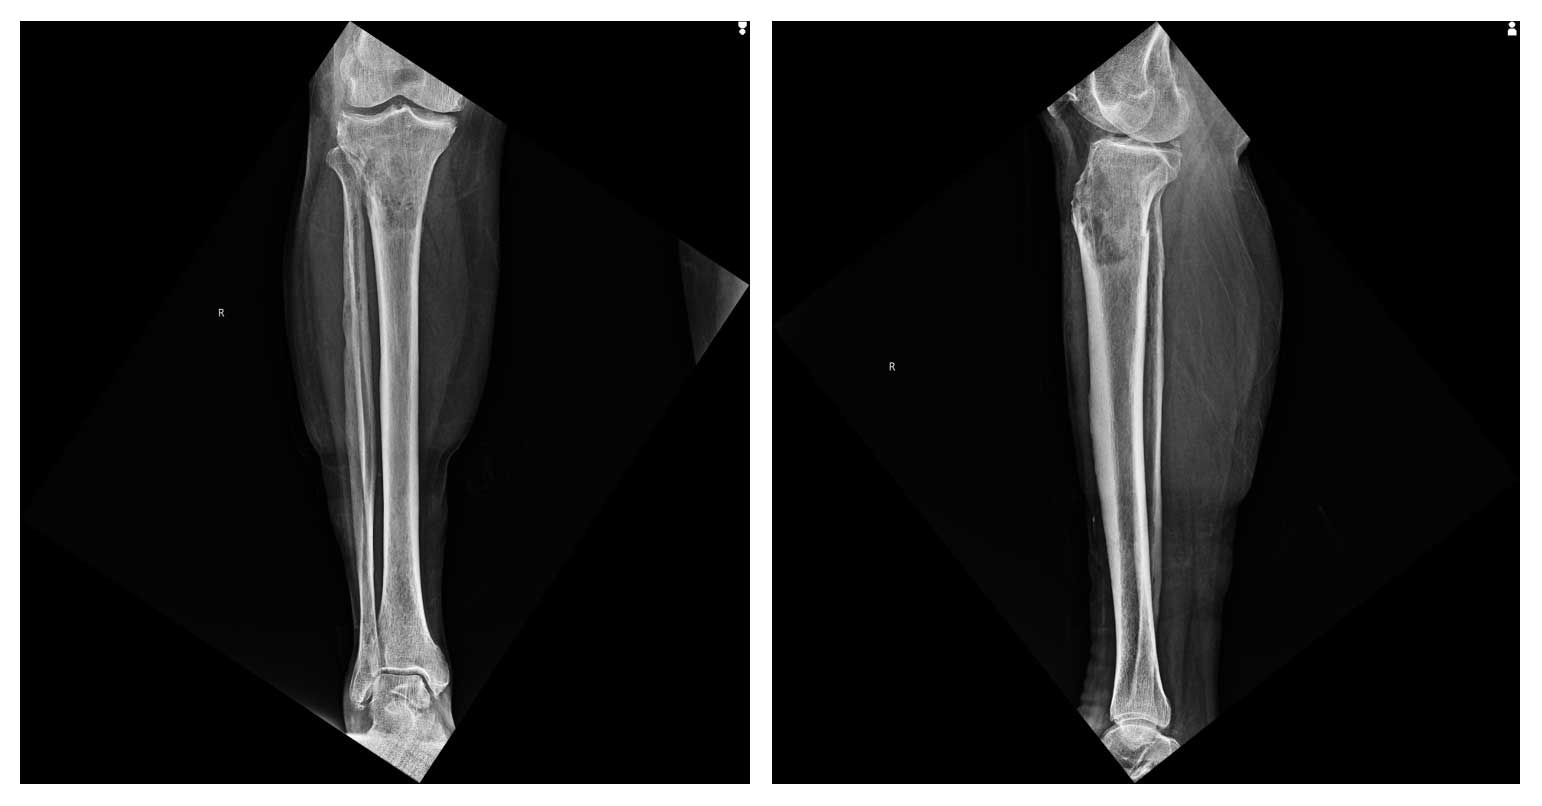

70 yaş erkek hasta, sağ diz çevresinde ağrı ve şişlik şikayetiyle başvurdu. Yapılan radyolojik incelemeler ve biyopsi sonucunda proksimal tibia osteosarkomu tanısı konuldu.

Ameliyat Öncesi: Röntgende proksimal tibia yerleşimli düzensiz sınırlı kemik harabiyetine neden olan kitle görülmekte.